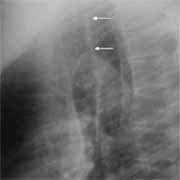

(radiol.) Una opacidad lineal orientada verticalmente, de una amplitud entre 2 y 5 mm., la cual se extiende desde la entrada torácica superior hasta la bifurcación de la tráquea y visible sólo en la radiografía lateral del tórax. Está situada entre la sombra aérea de la tráquea y el pulmón derecho y está formada por la pared traqueal posterior y tejido mediastinal adyacente. (figuras 3a y 3b).

| Figura 3a. Radiografía lateral de tórax: Banda traqueal posterior (flechas). | Figura 3b. TAC mostrando Banda traqueal posterior con pulmón derecho en el receso supraácigos. |